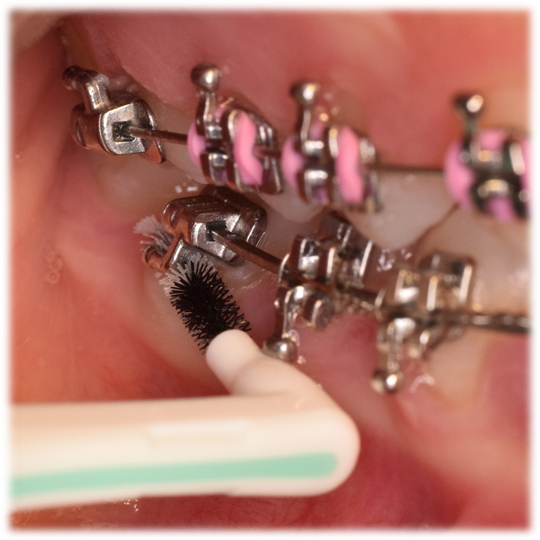

Su uso durante el tratamiento ortodóntico (Fig. 6) trae grandes beneficios ya que los dispositivos de ortodoncia son grandes retenedores de placa. Se aconseja su uso alrededor de los cuatro lados del bracket (Fig. 6) y con especial cuidado bajo tubos bucales (Fig. 7) y hooks (Fig. 8, 9 y 10).